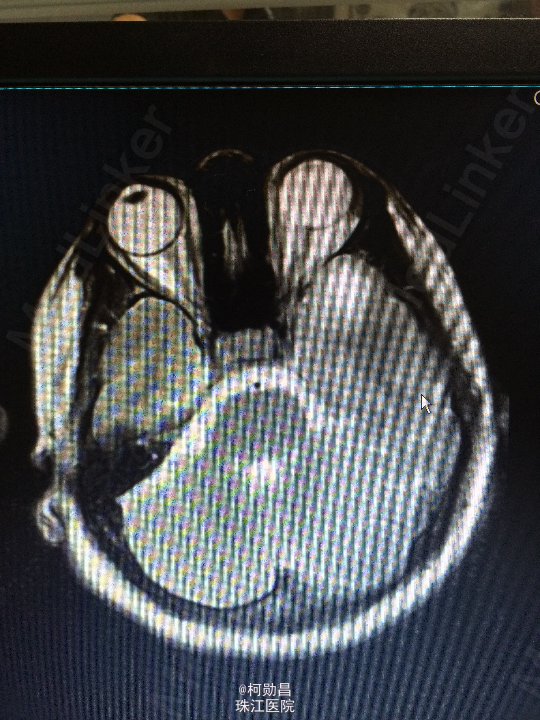

间断性眩晕伴头痛10余年 患者10年来无明显诱因间断性出现起床后眩晕,为天旋地转状,伴头痛、恶心、呕吐,严重时会出现肢体抽搐,双眼紧闭,无口角抽搐、意识障碍等。大约每年发作一次,数小时后自行好转,自服药物治疗(具体不详)。患者1个月前再次出现上述症状,遂至我院诊治:查头颅MR提示:左侧颞极前部皮层及皮层下异常信号影,不排除肿瘤。建议增强扫面。

查体:神经系统查体未见明显异常 头颅CT:左颞极前部占位,建议增强检察 头颅MR:左侧颞极前部皮层及皮层下异常信号影,不排除肿瘤。

诊断:脑膜血管瘤 处理:开颅手术切除,术后病理提示:(左颞极)脑膜血管瘤